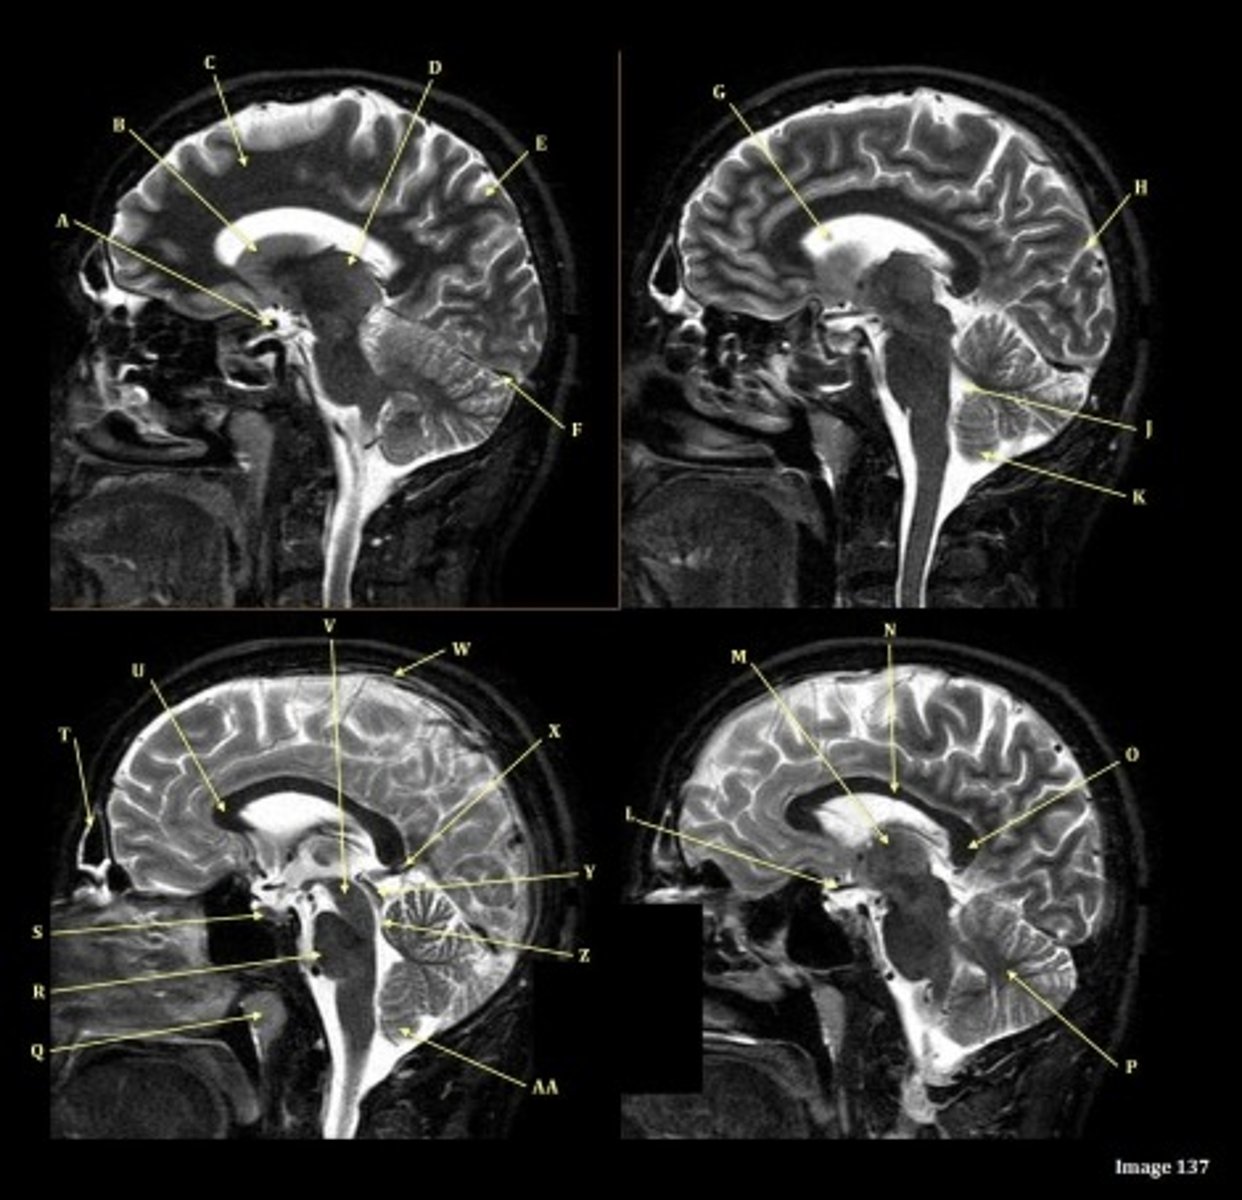

What type of sequence?

T2 FLAIR; Sagittal

A FLAIR (Fluid Attenuated Inversion Recovery) sequence is utilized to suppress signal from cerebrospinal fluid (CSF).

A

lateral ventricle

B

corpus callosum

C

thalamus

D- separates what

tentorium cerebelli- cerebrum (occipital and temporal lobes) from brainstem and cerebellum

E

fourth ventricle

F

medulla oblongata

Internal carotid artery

Caudate nucleus

white matter

D

straight sinus

G

H

lateral sulcus

L

optic chiasm

O

Splenium of corpus callosum

V

Cerebral peduncle

W

superior sagittal sinus

X

vein of galen

Y

Inferior colliculus of midbrain,

just inferior to pineal gland / superior to the cerebral aqueduct

Letter N in Image 137 is pointing to what type of tissue?

The corpus callosum is the only white matter tissue structure found in the midline sagittal slice of the brain.